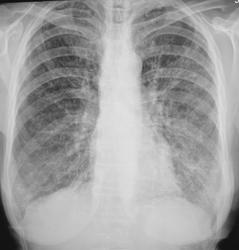

Контроль после флюорографии.

Первая мысль о саркоидозе или мтс.

Думаю пневмофиброз по типу силикоза.

Или фиброзирующий альвеолит.

+1 за дифузный пневмофиброз...может просто ХОЗЛ и всего то...

Фиброзирующий альвеолит

ХНЗЛ

кажись,еще слева парааортально в верхем поле булла...

Валентин Львович, тут явно синдром патологии легочного рисунка и очаговой диссиминации. Не исключаны туберкулез и канцероматоз. Тут нужна клиника и лабораторное подтверждение. Может быть неспецифический процесс в плане отравления металлами, пылью или еще чем. А возможно и редкость какая - типа васкулита.

Да, пациент консультирован в ОПТД, взят на учёт

То, что "взят" не факт , что туб. Не миллиарный, диссеминация разноочаговая, но фиброзирующий альвеолит не отрицается.

Но рост "палки" на средах - это факт и факт довольно весомый!

Коллеги, а к какому классу отнести данный вариант туберкудеза? К диссеминированному? Спасибо.

Диссеминированный туберкулёез лёгких. См. http://www.radiomed.ru/publications/tuberkulez-klinicheskaya-klassifikatsiya-tuberkuleza